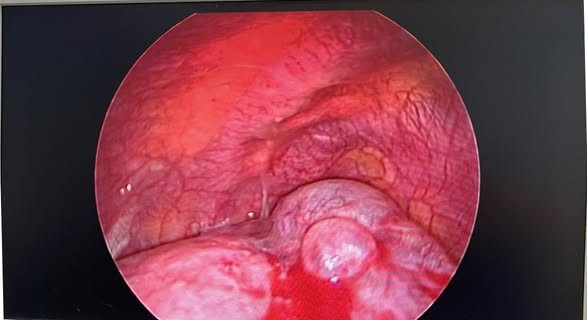

Hình ảnh kén khí phổi vỡ - Ảnh BVCC

Trong quá trình phẫu thuật, ê-kíp lần lượt cắt chùm bóng khí đỉnh phổi phải, khâu phục hồi nhu mô phổi, gỡ dính màng phổi phải, cải thiện chức năng hô hấp cho bệnh nhân.